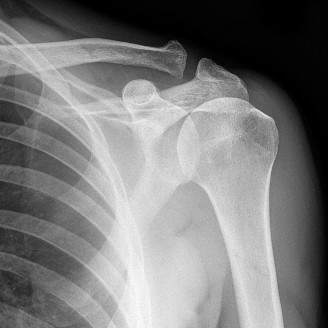

Treat a patient with infected total shoulder arthroplasty? CASE 21 A 70-year-old, right-hand-dominant female presents to clinic complaining of 4 years of gradually worsening chronic right shoulder pain and stiffness. She says the pain is worse at night and with any range of motion, denies a history of trauma, pain in other extremities, or numbness or tingling of the right upper extremity. She notes that her mother suffered from rheumatoid arthritis that affected her shoulder. Physical examination reveals decreased muscle bulk over the right supra- and infraspinatus fossae compared to the contralateral side, limited active and passive ROM, marked weakness with external rotation, and 4+/5 strength with shoulder abduction. X-rays of the right shoulder are shown in Figures 2–58 and 2–59.

Figure 2–58

Figure 2–59

The correct answer is (C). Rotator cuff tear arthropathy consists of a combination of rotator cuff insufficiency, glenohumeral joint degenerative changes, and superior humeral head migration. It is more common in women and also more often found on the dominant side. The patient’s clinical examination with weakened external

rotation and muscle atrophy signaling incompetent supra- and infraspinatus muscles point to rotator cuff insufficiency, and her plain films reveal narrowed glenohumeral joint space as well as superior migration of the humeral head. Choice D is incorrect because, while radiographs would show narrowing of the glenohumeral joint space, they would also likely show numerous osteophytes and posterior wear of the glenoid. Choice B is incorrect because, while adhesive capsulitis does present as decreased active and passive range of motion, the patient’s constellation of symptoms pointing towards rotator cuff insufficiency along with the radiographs make cuff tear arthropathy the more likely choice. Finally, Choice A is incorrect because even though she has a positive family history of rheumatoid arthritis, it is less likely to present only in a single joint. Also, rheumatoid arthritis on radiography appears more as an erosive process without the characteristic superior migration of the humeral head.

The correct answer is (A). Superior migration of the humeral head would be most indicative of chronic rotator cuff insufficiency associated with cuff tear arthropathy, as it is a direct result of the inability of the rotator cuff tendons to help maintain the humerus in its normal position. Acetabularization of the undersurface of the acromion is commonly associated with superior migration of the humeral head found in rotator cuff tear arthropathy, and can be assessed using the Hamada classification, which is based on measurements of the acromiohumeral interval on radiography (Table 2–8). Choices B and C are incorrect because, while narrowed glenohumeral joint space and subchondral sclerosis are associated with rotator cuff arthropathy on radiographs, they indicate degenerative joint changes rather than chronic rotator cuff insufficiency. Choice D is incorrect because it is not a specific sign of rotator cuff arthropathy.